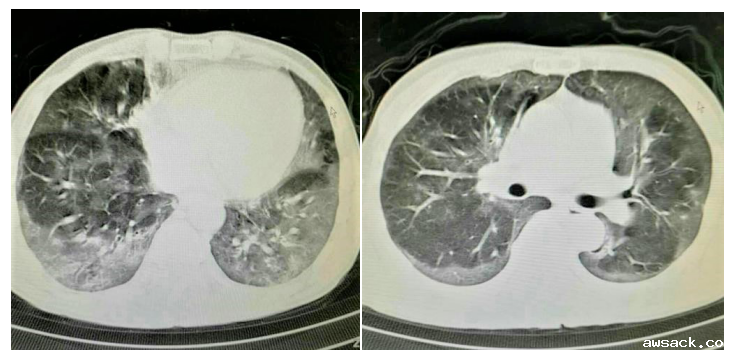

百草枯为何如此可怕?因为一旦中毒,留给您的只有后悔的时间,却鲜有存活的机会。百草枯毒性累及全身多个脏器,严重时可导致多器官功能不全综合征(MODS),其中肺是主要靶器官,可导致“百草枯肺”,早期表现为急性肺损伤(ALI)或急性呼吸窘迫综合征(ARDS),后期则出现肺泡内和肺间质纤维化,是百草枯中毒患者致死的主要原因,病死率高达50%~70%。

百草枯肺

在儿童重症医学科,误服百草枯的多为幼儿和学龄前儿童。部分学龄期、青春期患儿,因为和父母吵架置气,抑或早恋,一时糊涂就自服了百草枯。早期喝下百草枯的患儿,身体不会有任何不适,甚至有些孩子觉得没有效果还会喝第二次、第三次…。百草枯中毒早期表现为化学性口腔炎、上消化道腐蚀性溃疡、肝肾损害,转而出现进行性肺部损伤,肺组织纤维化,最后因呼吸衰竭而活活“憋死”,生命永远定格在了如花的年纪,可谓教训惨痛。